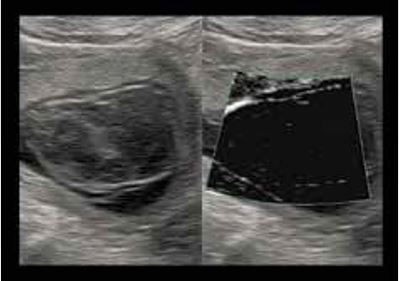

Субхоріальна гематома (мал. 4)

Субхоріальна гематома, яка в деяких випадках може бути дуже великою, це порівняно звичайне явище, яке не свідчить про якусь значну патологію. Повна відсутність кровопостачання, підтверджена відсутністю сигналу під час УЗД за технологією SMI, виключає діагноз хоріоангіоми і, отже, небезпеку гемодинамічних порушень. Утворення гематоми та її подальша реабсорбція призводять до виникнення субхоріальної кісти.

Мал. 4. Диференційна діагностика: субхоріонічна гематома